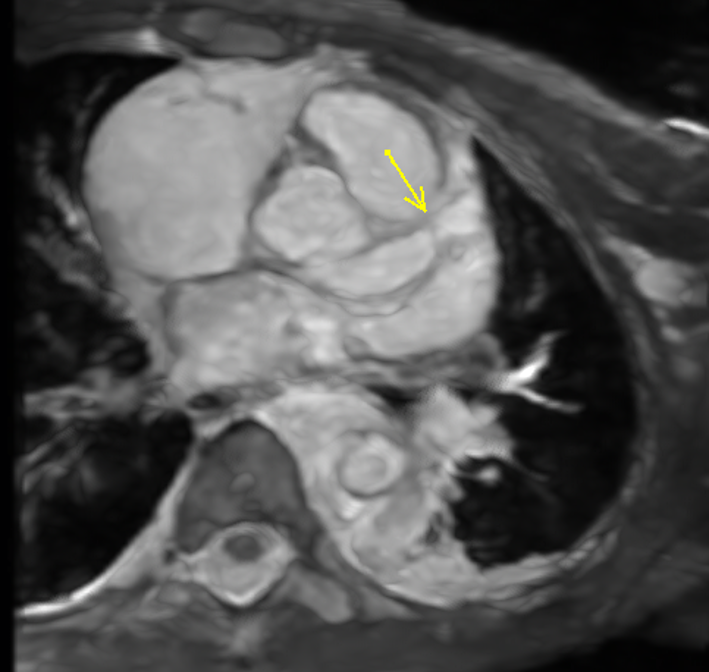

Diagnostic Techniques and Their Most Important Findings: MR angiography of the chest, abdomen, and pelvis (SIGNA Artist, GE Health, 1.5T) was performed. High resolution, post-contrast cardiac-gated 3D SSFP imaging of the chest (3D Whole Heart) was obtained and demonstrated marked irregularity and fusiform dilation of the aorta extending from the aortic arch through the iliac bifurcation (Image 1). There was severe dilatation of the left main coronary artery and proximal left anterior descending artery with normal sized coronary at the bifurcation (Image 2). Tissue characterization with fat-saturated pre- and post-contrast T1 weighted and T2 weighted sequences was performed. These demonstrated marked aortic wall thickening and enhancement consistent with active inflammation (Image 3). Findings were felt to be consistent with Takayasu arteritis with coronary involvement. He was started on heparin and methylprednisone and transitioned to clopidogrel, aspirin, rivaroxaban, optic and systemic prednisone, and infliximab infusion as an outpatient.

Image 2: Severe dilatation of the left main coronary artery and proximal left anterior descending artery with normal sized coronary at the bifurcation.

Image 2: Severe dilatation of the left main coronary artery and proximal left anterior descending artery with normal sized coronary at the bifurcation.

Diagnostic Techniques and Their Most Important Findings: MR angiography of the chest, abdomen, and pelvis (SIGNA Artist, GE Health, 1.5T) was performed. High resolution, post-contrast cardiac-gated 3D SSFP imaging of the chest (3D Whole Heart) was obtained and demonstrated marked irregularity and fusiform dilation of the aorta extending from the aortic arch through the iliac bifurcation (Image 1). There was severe dilatation of the left main coronary artery and proximal left anterior descending artery with normal sized coronary at the bifurcation (Image 2). Tissue characterization with fat-saturated pre- and post-contrast T1 weighted and T2 weighted sequences was performed. These demonstrated marked aortic wall thickening and enhancement consistent with active inflammation (Image 3). Findings were felt to be consistent with Takayasu arteritis with coronary involvement. He was started on heparin and methylprednisone and transitioned to clopidogrel, aspirin, rivaroxaban, optic and systemic prednisone, and infliximab infusion as an outpatient.

Image 2: Severe dilatation of the left main coronary artery and proximal left anterior descending artery with normal sized coronary at the bifurcation.

Image 2: Severe dilatation of the left main coronary artery and proximal left anterior descending artery with normal sized coronary at the bifurcation. Image 3: Pre- and post-LAVA of descending aorta showing marked aortic wall thickening and enhancement consistent with active inflammation.